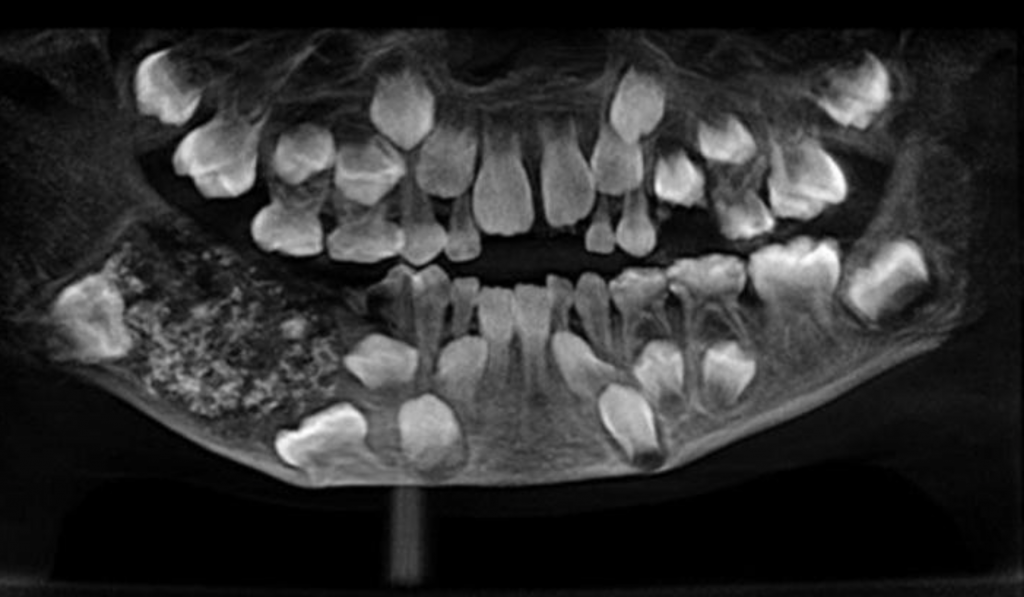

Dentistas de la India confirmaron que encontraron 526 piezas dentales extra en la boca de un pequeño que acudió a la consulta con dolor de mandíbula.

El centro médico Saveetha Dental College and Hospital en Chennai, India, dijo que el niño de tres años de edad ingresó con una hinchazón en la boca, pero nunca esperaron encontrar esa desmesurada cifra de dientes.

El hecho ha supuesto el primer caso médico de semejantes características documentado en la historia del hospital.